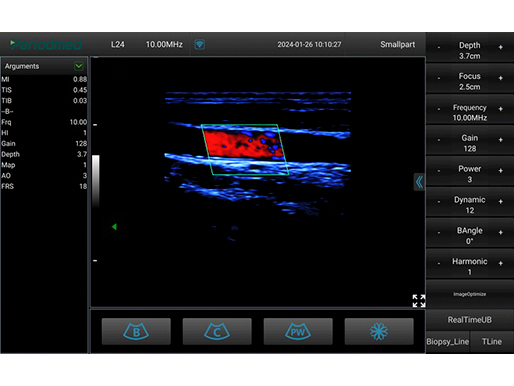

线阵探头-彩色模式-颈动脉